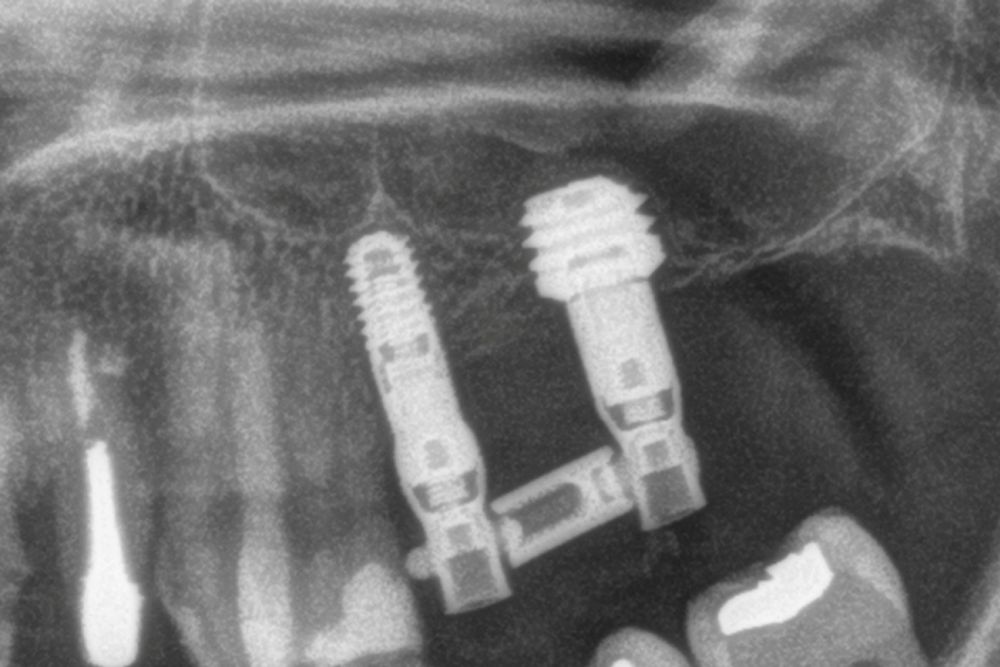

El acceso final a la cortical sinusal se efectuó con una fresa específicamente diseñada para esta técnica (fresa de corte frontal), la cual permite la eliminación controlada del suelo del seno maxilar sin comprometer la integridad de la membrana de Schneider10. Una vez expuesta la membrana a través de la perforación en la cresta ósea, se realizó su elevación de manera controlada, colocándose el injerto consistente en hueso autólogo obtenido del fresado de otras localizaciones en las que se colocan implantes en el mismo acto quirúrgico embebido en PRGF-Endoret. Por último, la colocación del implante se llevó a cabo con un motor quirúrgico calibrado a 25 Ncm y 25 rpm, mientras que la inserción final se realizó manualmente mediante una llave dinamométrica para asegurar una fijación óptima (Figura 1).

En las Figuras 7- 13 se muestra uno de los casos incluidos en el estudio.